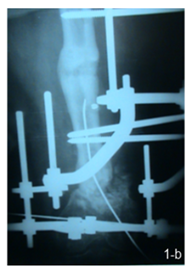

16 patients were operated by a single stage strategy with debridement of the fracture site through lateral approach with thorough excision of all infected tissues and necrotic bone and then fixation with ilizarov or uniplaner external fixation was done with acute shortening and compression at the fracture site in patients with bone defects of 2 cm or less, and use of autogenous cancellous bone graft was done in patients with bone defects more than 2 cm. (Figure 1 a, b & c).

Figure 1 a) Femoral infected non union. b) Postoperative by single stage, and c) After union.